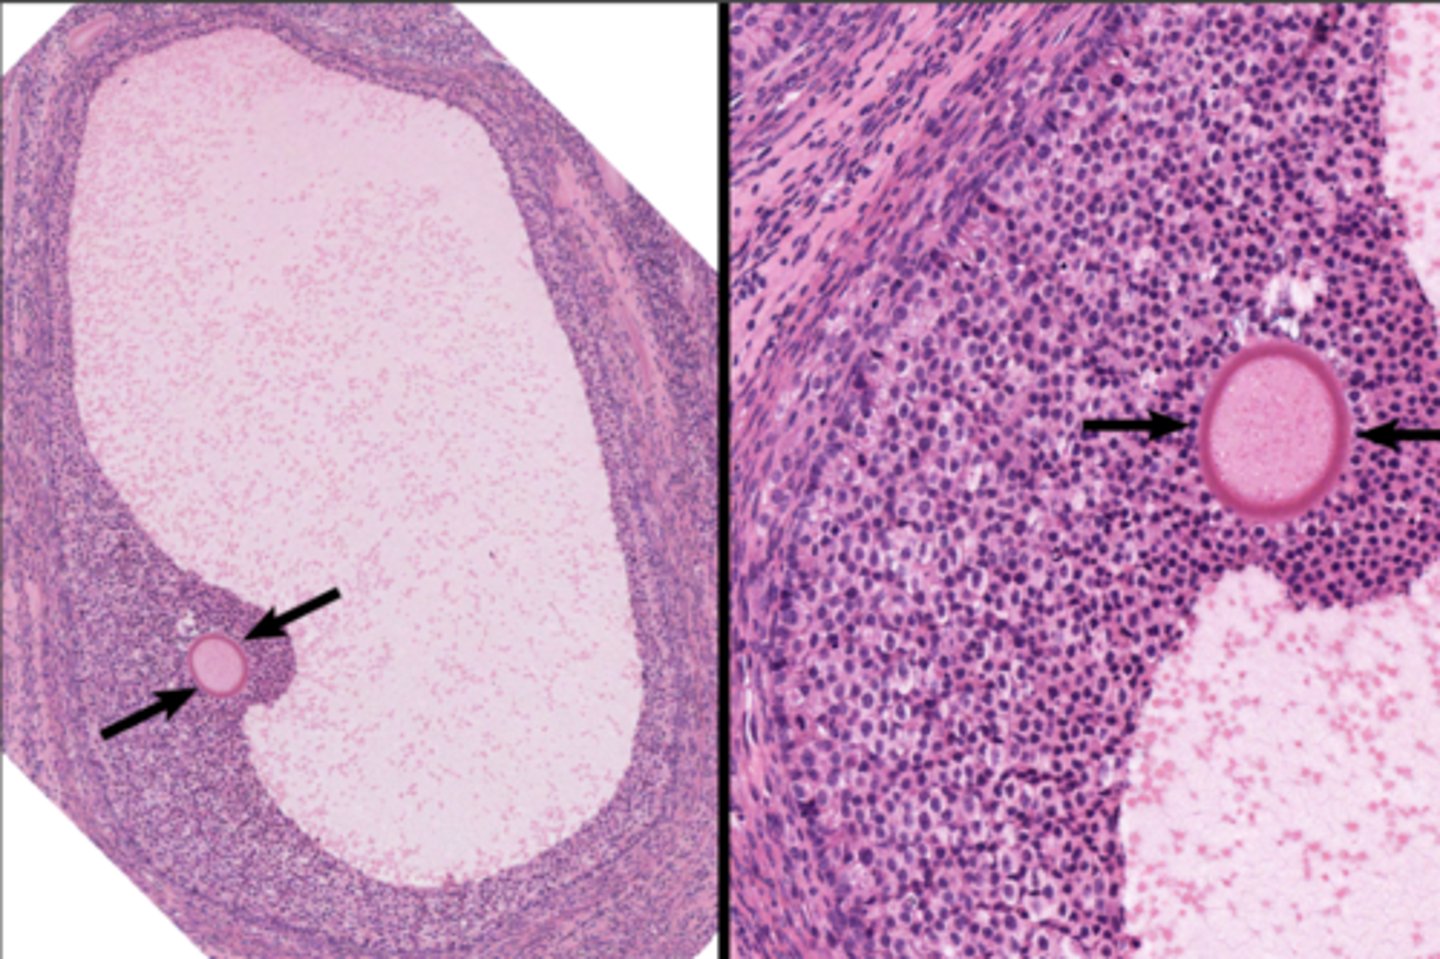

Corpus luteum

Corpus luteum

Corpus albicans

Corpus albicans

corpus luteum

8

early corpus luteum

9

late corpus luteum

10

corpus albicans

11

granulosa cells

12

theca cells

13

antrum

14